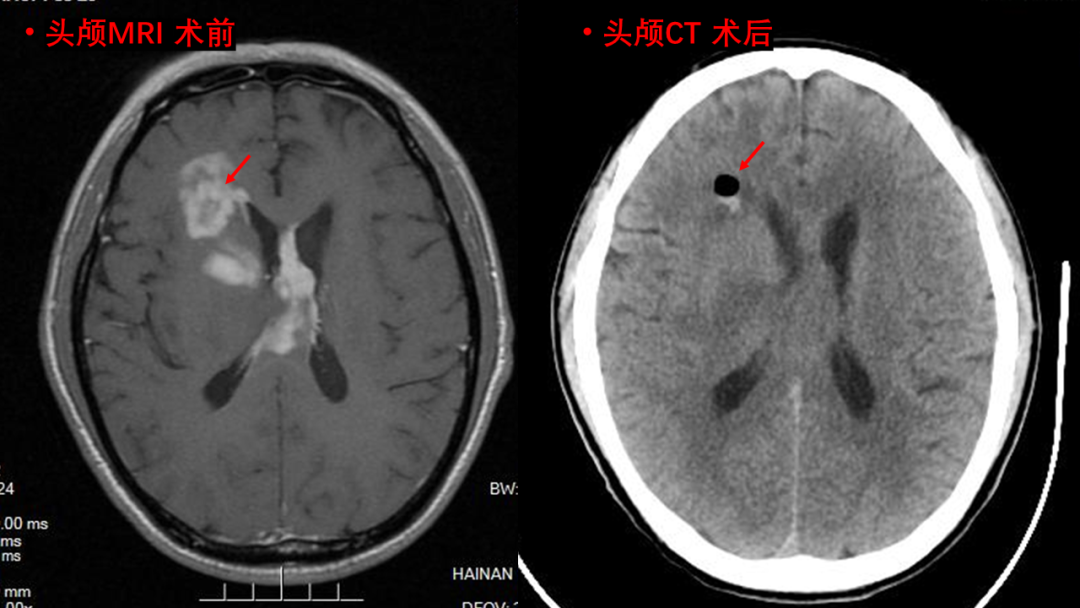

在给予周先生对症治疗后,神经医学中心立即组织多学科会诊,一致认为周先生发病时间较短,脑内病变部位位于重要功能区,病变范围广,诊断不明确,无法手术切除,决定实施立体定向颅内占位活检术,既能弥补影像学诊断对病变定性的不足,又避免开颅手术导致的神经功能损害,且定位准确,创伤小,安全可靠,并发症少,痛苦小,医疗费用较低。

张捷教授与冯雨主任对周先生进行术前MRI、CT定位

术中,在麻醉科、手术室的通力协作下,成功为周先生在全麻下进行了立体定向颅内病变活检术。手术过程顺利,当日复查CT,显示穿刺部位无出血,术后恢复良好。术后病理诊断结果:胶质母细胞瘤,WHO Ⅳ级。